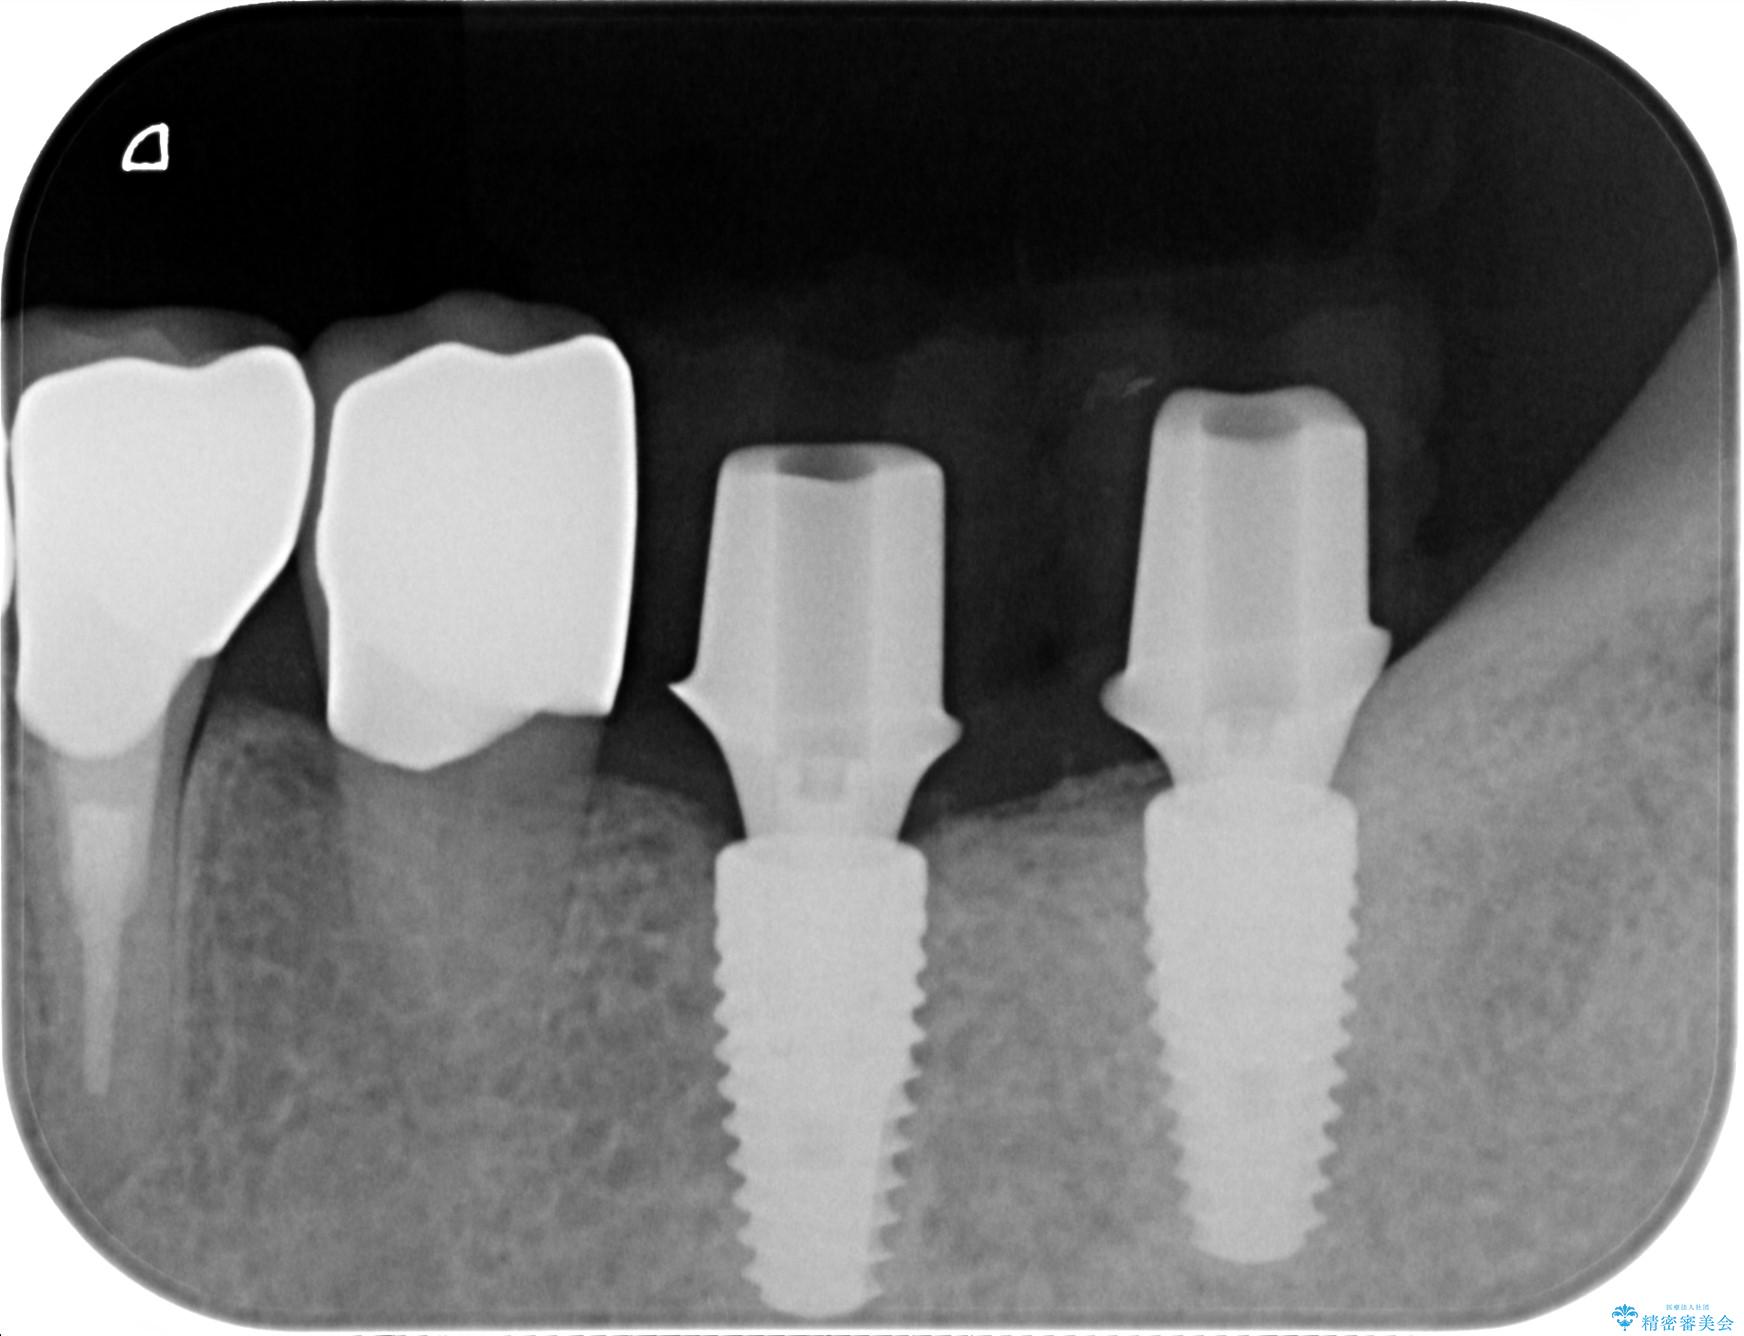

治療中

劣化の進んだブリッジの再治療[ 不適合な補綴物による虫歯の再発 ] 治療中画像 劣化の進んだブリッジの再治療[ 不適合な補綴物による虫歯の再発 ] 治療中画像 劣化の進んだブリッジの再治療[ 不適合な補綴物による虫歯の再発 ] 治療中画像

• 概算治療費:125.4万円(インプラント×2・チタンカスタムアバットメント×2・ジルコニアクラウン×4・インプラント用仮歯×2・仮歯×2)※費用は治療当時の料金となります